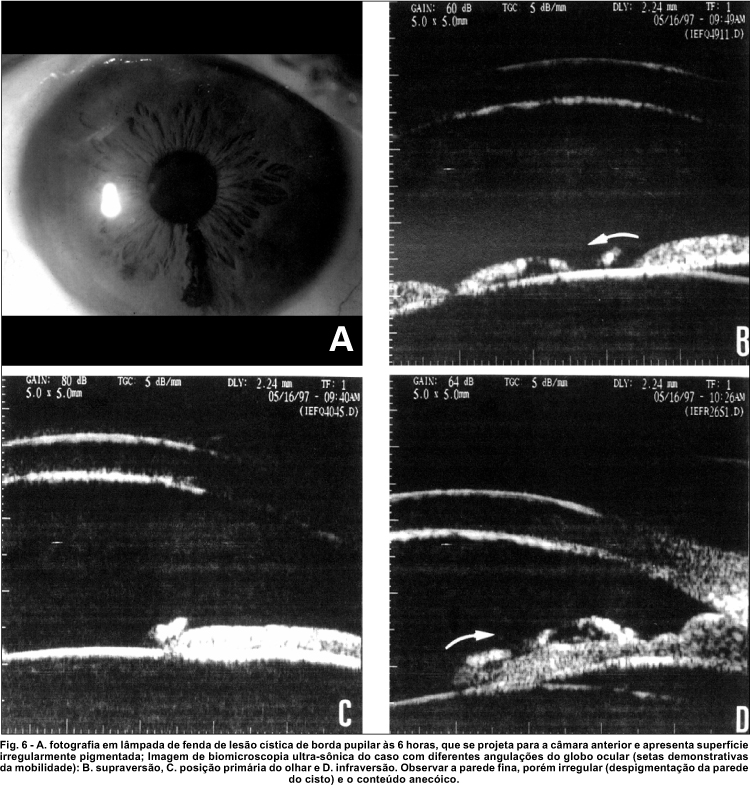

Outro caso interessante observado foi um cisto primário de íris localizado em borda pupilar, com configuração pedunculada, cuja extremidade livre assumia diferentes posições de acordo com o movimento ocular (figura 6).